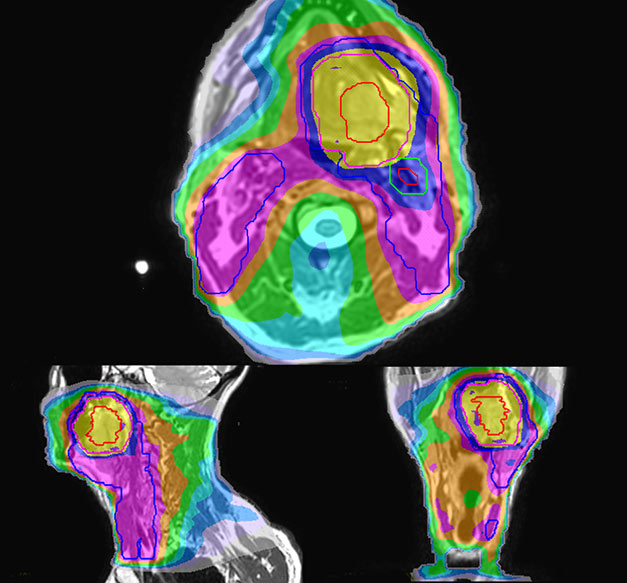

Epidermoid carcinoma of the left tongue base

The patient was diagnosed with an epidermoid carcinoma of the base of the left invading the amygdala lodge and the amygdaloglossal groove. Radiochemotherapy with curative aim was prescribed with a dose of 70 Gy for the tumor, 66 Gy on the suspicious nodes and 56 Gy on the elective drainage areas - in 33 fractions.

Personalized VMAT dose planned in Philips Pinnacle.